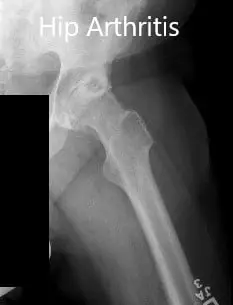

Imaging studies revealed severe bilateral osteoarthritis of the hips with subchondral cysts, sclerosis, and osteophytes. Considering the lifestyle limiting hip pain, she was advised bilateral total hip replacement. She agreed to go ahead with the procedure.

Preoperative X-ray showing the frog-leg lateral views of the right and the left hip joint.